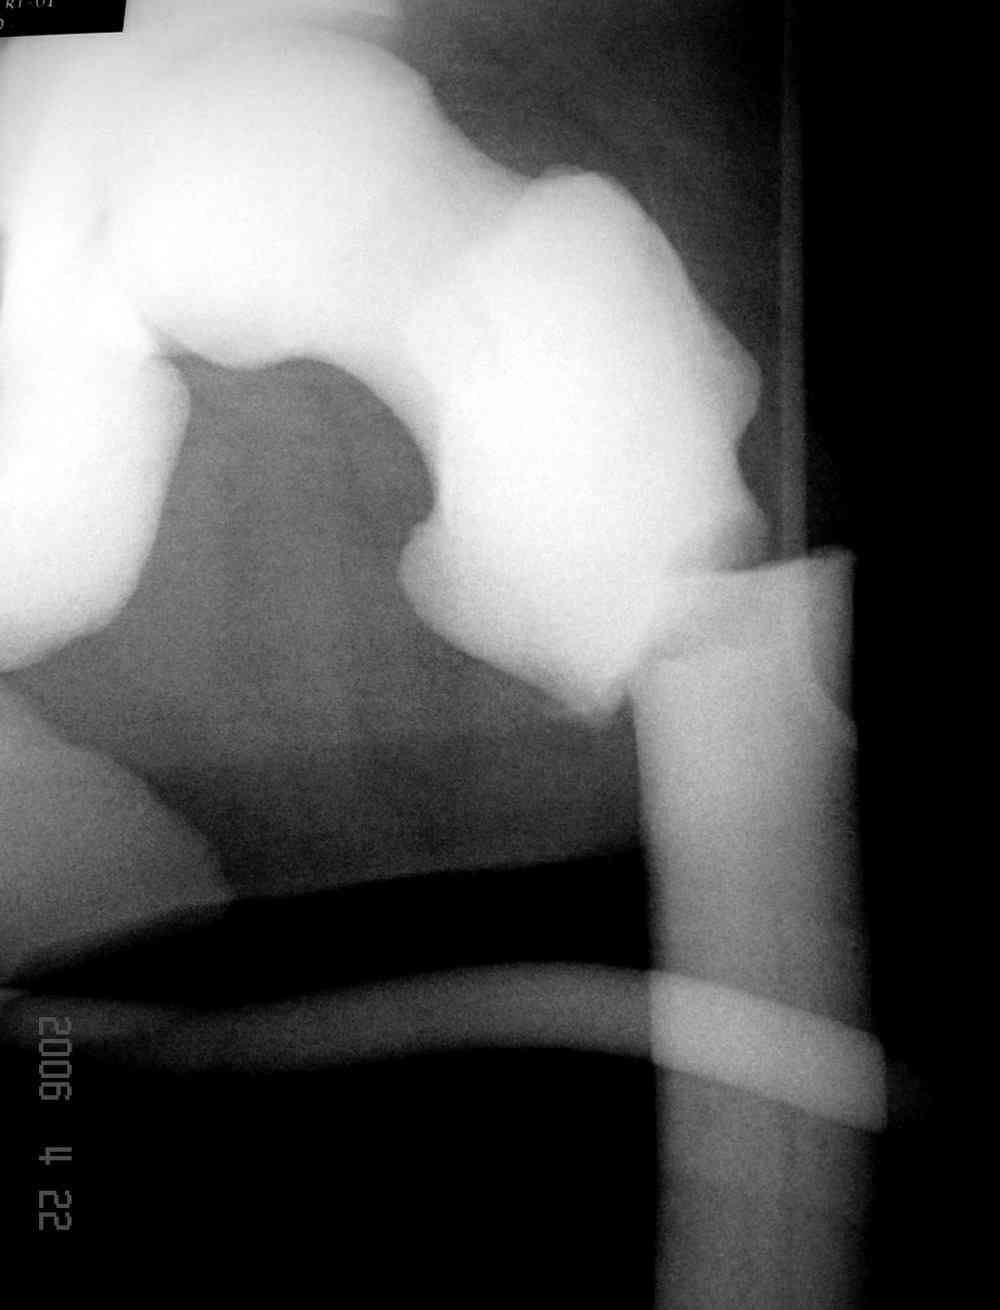

Здесь у меня дополнительные снимки с большим разрешением и в разных режимах, а то те дигитал снимки совсем очень блеклые, может, эти изображени изменят выбор тактики

После неудачной попытки скелетного вытяжения в первом мед.учреждении, после осмотра снимков и изучения истории, поставили диагноз “Остеопетроз” или мраморная болезнь, редкая наследственная костная паталогия, где имеется нарушение формации остеокластов.

Конечно, было бы идеальным применение интрамедуллярного остеосинтеза, но учитывая прежний собственный опыт (лечил перелом бедра) и

публикации, предупреждающие о трудностях при обработке кости (иногда из-за неподготовленности инструментария результатом была неадекватная фиксация перелома, или перенос операции из-за фактора усталости оперирующего персонала), решили применить пластину (и в этом же случае был выбран Synthes plate, так что представитель за два дня

Заказаны были дополнительные различные дрели, и на следующий день, усиленной бригадой, больного прооперировали, потратив на каждое отверстие около 25-35 минут, хотя сверлили с охлаждением по нарастающей по диаметру сверл и с их заменой каждые 2 мм сверления.

Теперь стоит задача со сращением перелома, из-за отсутствия литературных данных по применению костных стимуляторов при остеопетрозе, и не зная как поведет в этой среде Grafton, все таки надеюсь, что даст толчок к стимуляцию, решил применить пастообразную деминерализованную костную матрицу, расположив спереди между отломками.